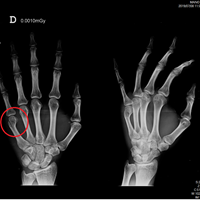

Yeso o férula para la recuperación de una fractura del boxeador (nudillo derecho)